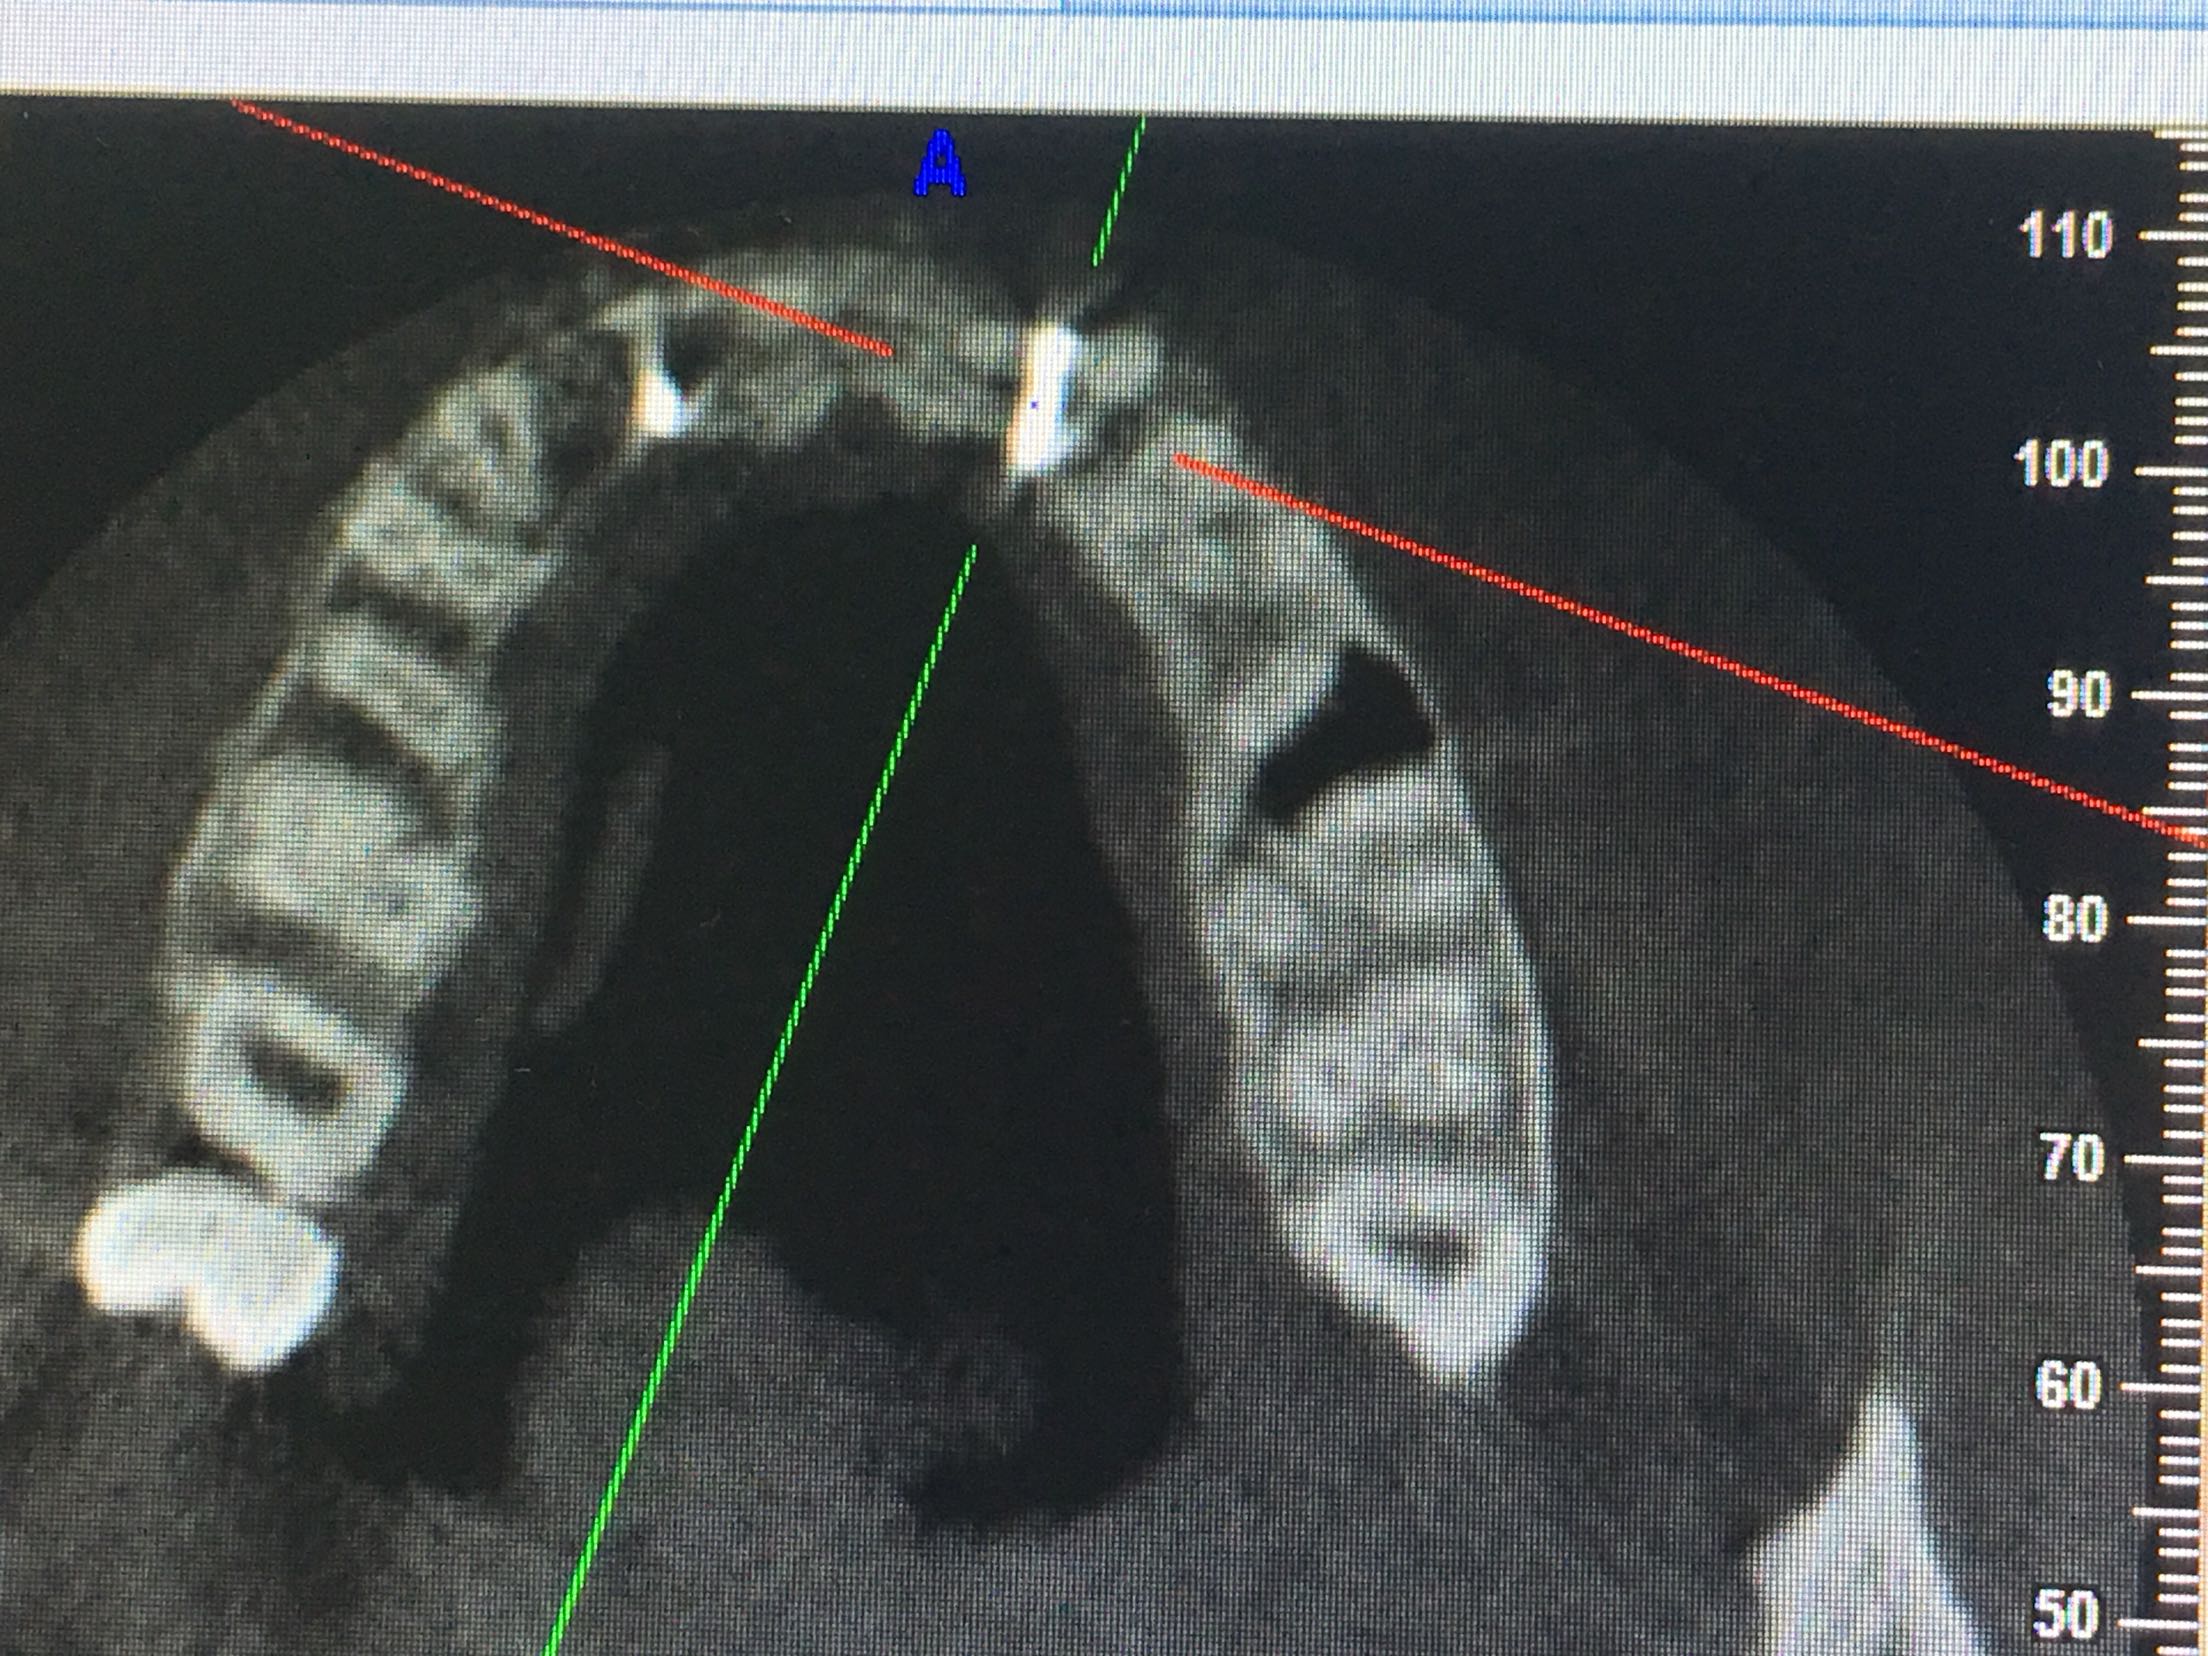

CBCT示11、12、21、22牙缺失,牙槽骨呈刀刃状,38、48牙阻生。

38、48牙超刀拔除,取双侧骨块,11、12、21、22梯形切口切开、翻瓣,切断粘骨膜松弛,骨块钛钉固定唇侧,植入Bio-ss骨粉0.5g,覆盖生物膜,严密缝合!嘱半年后种植!